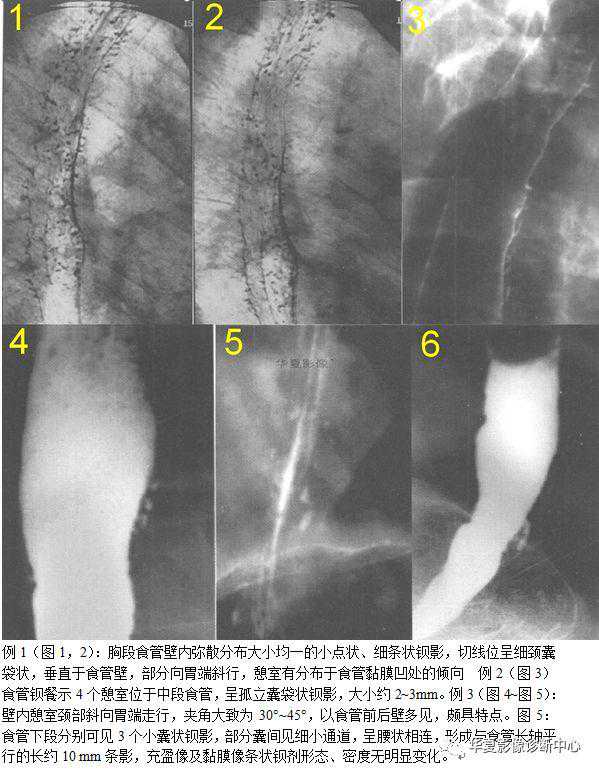

【影像表现】食管钡剂造影发现囊袋状憩室自腔内向外突出,憩室一般表现为食管壁内泪滴状或细颈瓶状钡剂积聚,直径0.5~2cm。

【征象解释】食管壁内假性憩室只是指食管黏膜下层腺体呈囊性扩张,并通过排泄管与食管腔内相通。食管黏膜下腺体在人类进化过程中处于逐渐退化的阶段,从理沦上推测。这种退化组织极其脆弱,某些内外因素可能使其呈囊状变性或继发感染,因此不需要特殊治疗,壁内轨道征是X线诊断食怜壁内憩室的特征性表现,提示炎症的扩散。

Cho等对一组EIP患者进行研究发现,50%的患者有壁内轨道征,并认为壁内轨道征多见于弥漫性者甲是食管壁内假性憩室的特征性表现,国内有学者认为所谓轨道应该是各个壁内憩室炎症继续扩展并向周围蔓延,并浸及相邻上下的憩室,致其融合形成所谓的轨道,因此各憩室间轨道不会过长,若出现长的索形轨道应该视为其并发症。壁内轨道征是X线诊断食管壁内憩室的特征性表现,提示炎症的扩散。食管壁内憩室颈管向足端斜向走行,为诊断壁内憩室的另一重要征象。这种斜行颈管光滑纤细,相邻食管壁光滑。皱璧规则,壁内憩室间无通道形成。